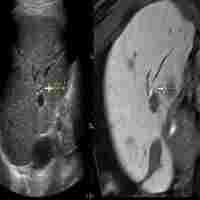

| Abstract | The ultrasound (US) imaging technology, including contrast-enhanced US (CEUS) and fusion imaging, has experienced radical improvement, and advancement in technology thus overcoming the problem of poor conspicuous hepatocellular carcinoma (HCC). On CEUS, the presence or absence of enhancement distinguishes the viable portion from the ablative necrotic portion. Using volume data of computed tomography (CT) or magnetic resonance imaging (MRI), fusion imaging enhances the three-dimensional relationship between the liver vasculature and HCC. Therefore, CT/MR-US fusion imaging provides synchronous images of CT/MRI with real-time US, and US-US fusion imaging provides synchronous US images before and after ablation. Moreover, US-US overlay fusion can visualize the ablative margin because it focuses the tumor image onto the ablation zone. Consequently, CEUS and fusion imaging are helpful to identify HCC with little conspicuity, and with more confidence, we can perform ablation therapy. CEUS/fusion imaging guidance has improved the clinical effectiveness of ablation therapy in patients with poor conspicuous HCCs. Therefore; this manuscript reviews the status of CEUS/fusion imaging guidance in ablation therapy of poor conspicuous HCC. |